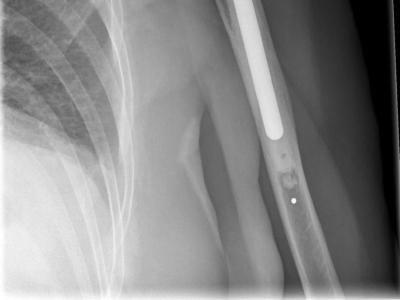

Without DMARDS, Shoulder Arthroplasty Increasing in Rheumatoid Arthritis The need for total shoulder arthroplasty (TSA

Without DMARDS, Shoulder Arthroplasty Increasing in Rheumatoid Arthritis The need for total shoulder arthroplasty (TSA) in rheumatoid arthritis (RA) patients appears to depend on the use of DMARDs, according to Seminars in Arthroplasty. https://t.co/iGAQaa7Ppc https://t.co/AbteC427wI